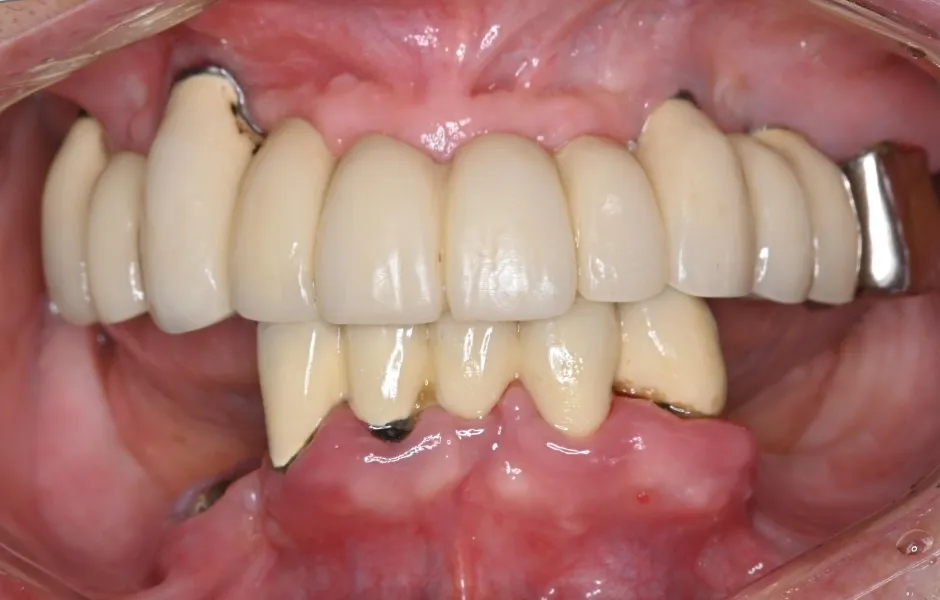

全顎治療・咬合治療

(歯がボロボロ)虫歯や歯周病が悪化して、歯を失っている・ボロボロのまま放置すると、機能性と審美性に影響がでます。お口のトラブルを改善できるよう、さまざまな治療をご提案します。

全顎治療・咬合治療(歯がボロボロ) -